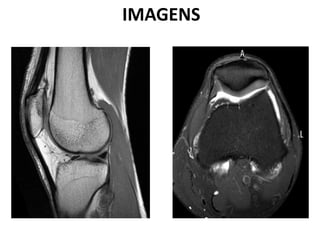

IMAGENS

ANATOMIA